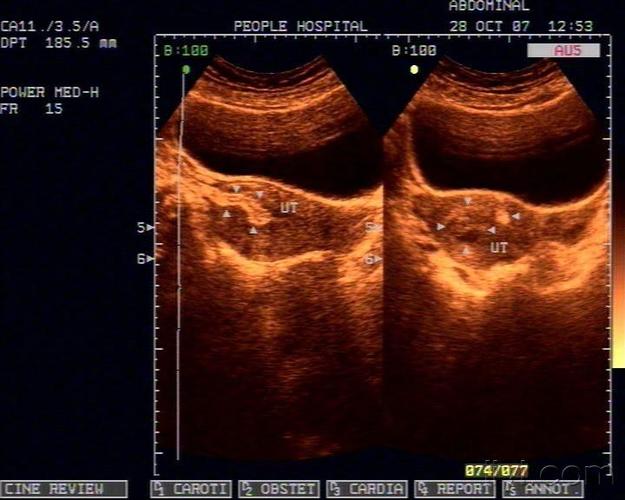

子宫穿孔彩超下表现

子宫穿孔彩超下表现,子宫穿孔超声表现图

典型人流术子宫穿孔

子宫穿孔的超声诊断

子宫穿孔超声表现图

子宫穿孔彩超图

子宫穿孔b超图片

子宫穿孔超声图片

正常子宫彩超图